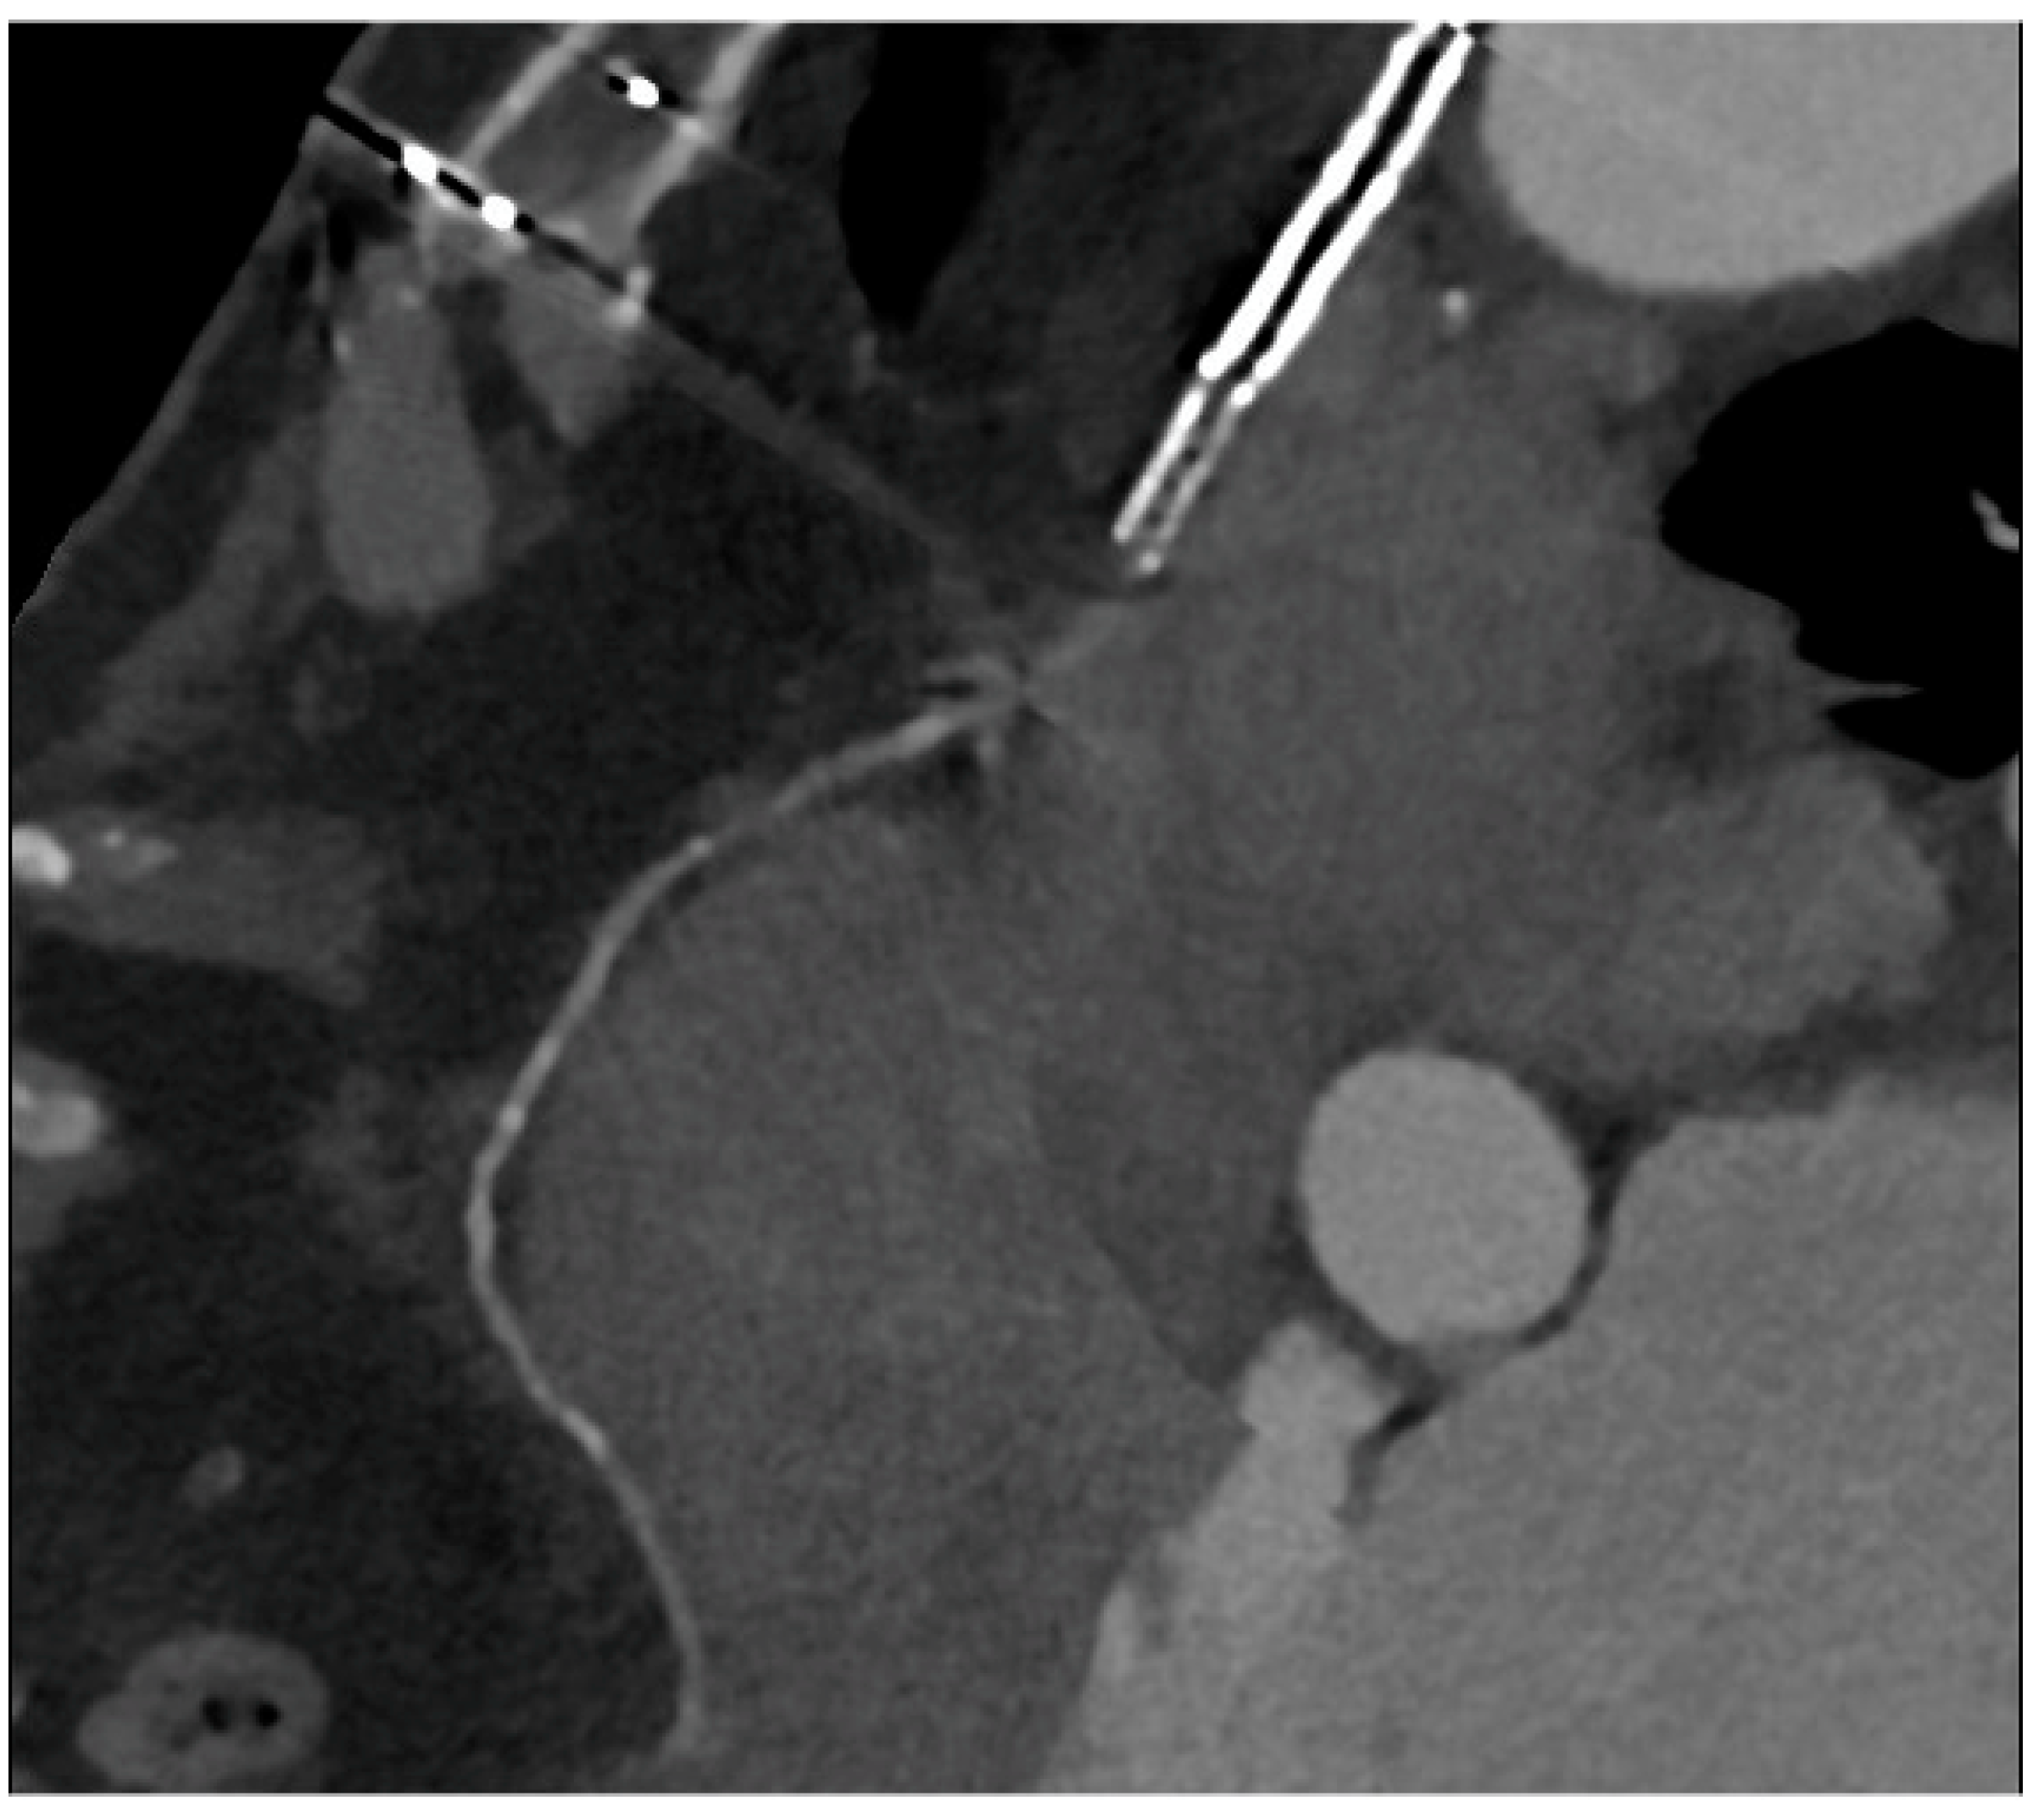

PCI of the left main (LM) improves survival, and in most cases, it is not inferior to surgical revascularization [14]. Intra-stent restenosis (ISR) is a complication of paramount importance, especially in the setting of LM revascularization, because of its relationship to adverse events. With current stents, ISR is due to neo-atherogenesis, which leads to a higher risk of destabilization and stent thrombosis. In the setting of LM, ISR at 15-month follow-up has been revealed to be present in up to 16% of total subjects, requiring invasive revascularization in 7% of cases. Coronary angiography represents the best technique for ISR assessment [14]. Planned Angiography Control (PAC) has been proposed to diagnose and treat ISR promptly, but its benefit remains to be established. An increased rate of percutaneous coronary interventions (PCI) without a reduction in cardiovascular events has been mainly reported. Some technical issues about the use of CCTA in coronary stent imaging have been described, such as the blooming effect, partial volume effect, motion artifacts, and inadequate intravascular contrast enhancement. The blooming effect is the most important issue, corresponding to a phenomenon in which stent struts appear thicker, causing an underestimation of stent lumen. However, with new technology development, CCTA provides a precise, noninvasive reconstruction of the coronary tree and may offer an alternative to invasive coronary angiography [15]. Figure 1 shows three multiplanar reconstructions of LM and left anterior descending with a drug-eluting stent previously implanted: struts of the stent appear clearly detectable, the stent seems to be well-positioned, and regarding stent lumen, it can be noted that there is good opacification and no evidence of ISR. Medium and distal tracts of the left anterior descending seem to be free from plaque proliferation and/or stenosis. Figure 2, instead, shows an ISR of a stent implanted in the proximal segment of the left circumflex coronary artery. Therefore, Figure 1 and Figure 2 demonstrate the feasibility of LM and proximal segment stent assessment by CCTA. Its use in the PAC setting has been investigated and may provide relevant advantages as it is a noninvasive examination. There are three different methods to determine the degree of ISR with CCTA: qualitative, semi-quantitative, and quantitative. The first technique provides that significant ISR (reduction of luminal diameter >50%) is visually detected: ISR is identified as a hypodense layer between the struts and the lumen. The second method is characterized by a four-point scale where 1 corresponds to the patency of the stent and 4 results in stent occlusion. Finally, the third technique provides that the percentage of stenosis is calculated as the ratio between diameters in the short axis of the narrowest stent lumen and of the proximal and distal reference segments [15]. Roura G et al. evaluated the agreement between CCTA and intravascular ultrasound (IVUS) to assess in-stent lumen diameters and lumen area of LM stents: the study highlighted a good agreement between the two techniques so that CCTA can be considered to analyze LM ISR [4]. A study by Van Mieghem CAG et al. assessed the performance of CCTA in the analysis of LM stenting: they enrolled 74 patients scheduled for follow-up coronary angiography after LM stenting, and they performed CCTA before coronary angiography. The study demonstrated that the accuracy of CCTA for detecting LM ISR was 98%; in particular, diagnostic accuracy was 98% both for patients with stented LM and with distal LM bifurcation lesions and only one side branch treated [5]. In subjects with complex bifurcation stenting (i.e., LM and both major side branches), the reliability of CCTA was 83%. The low number of false-positive scans leading to unnecessary diagnostic coronary angiograms should be acceptable, taking into account the potentially serious consequences of LM ISR [5]. Furthermore, the study underlined that the evaluation of stent diameter and area by CCTA had a good correlation with IVUS assessment. One of the most important issues arising from this study was the high radiation dose required for the analysis of stents by CCTA. However, as previously reported, new scanner developments (i.e., dual-source CT scanners) reduced patient dose.

Figure 1.

CCTA assessment of left main drug-eluting stent (Lumen image on the left, multiplanar reconstruction in the center and on the right). With a new CT scan, beam-hardening artifacts are reduced, and the stent lumen can be assessed with good performance.